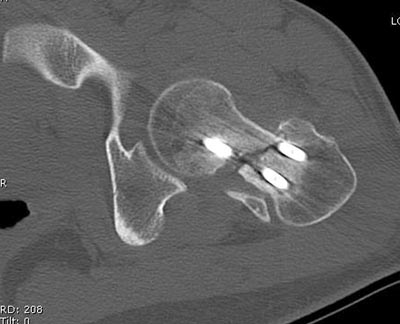

Здесь выставлен ренгенограммы больного, ему 21, травму получил в результате высокоскоростной погони на украденной машине, которая закончилась смертью трех остальных “боевых комрадов”. Начатую коллегой открытую операцию на шейке пришлось закончить мне, установкой винтов и ретроградной фиксацией бедра. Выписка в обычное сроки и наблюдался амбулаторно. Каждый раз напоминали о возможности осложнений ввиде несращения! По истечению 4 месяцев появились признаки варусной деформации. На СТ срезах несращение шейки и бедра. Риминг, замена на более толстый гвоздь и вальгусная остеотомия.

КТ тазобедренного и коленного суставов сделали - картина удручающая, постараюсь выложить.